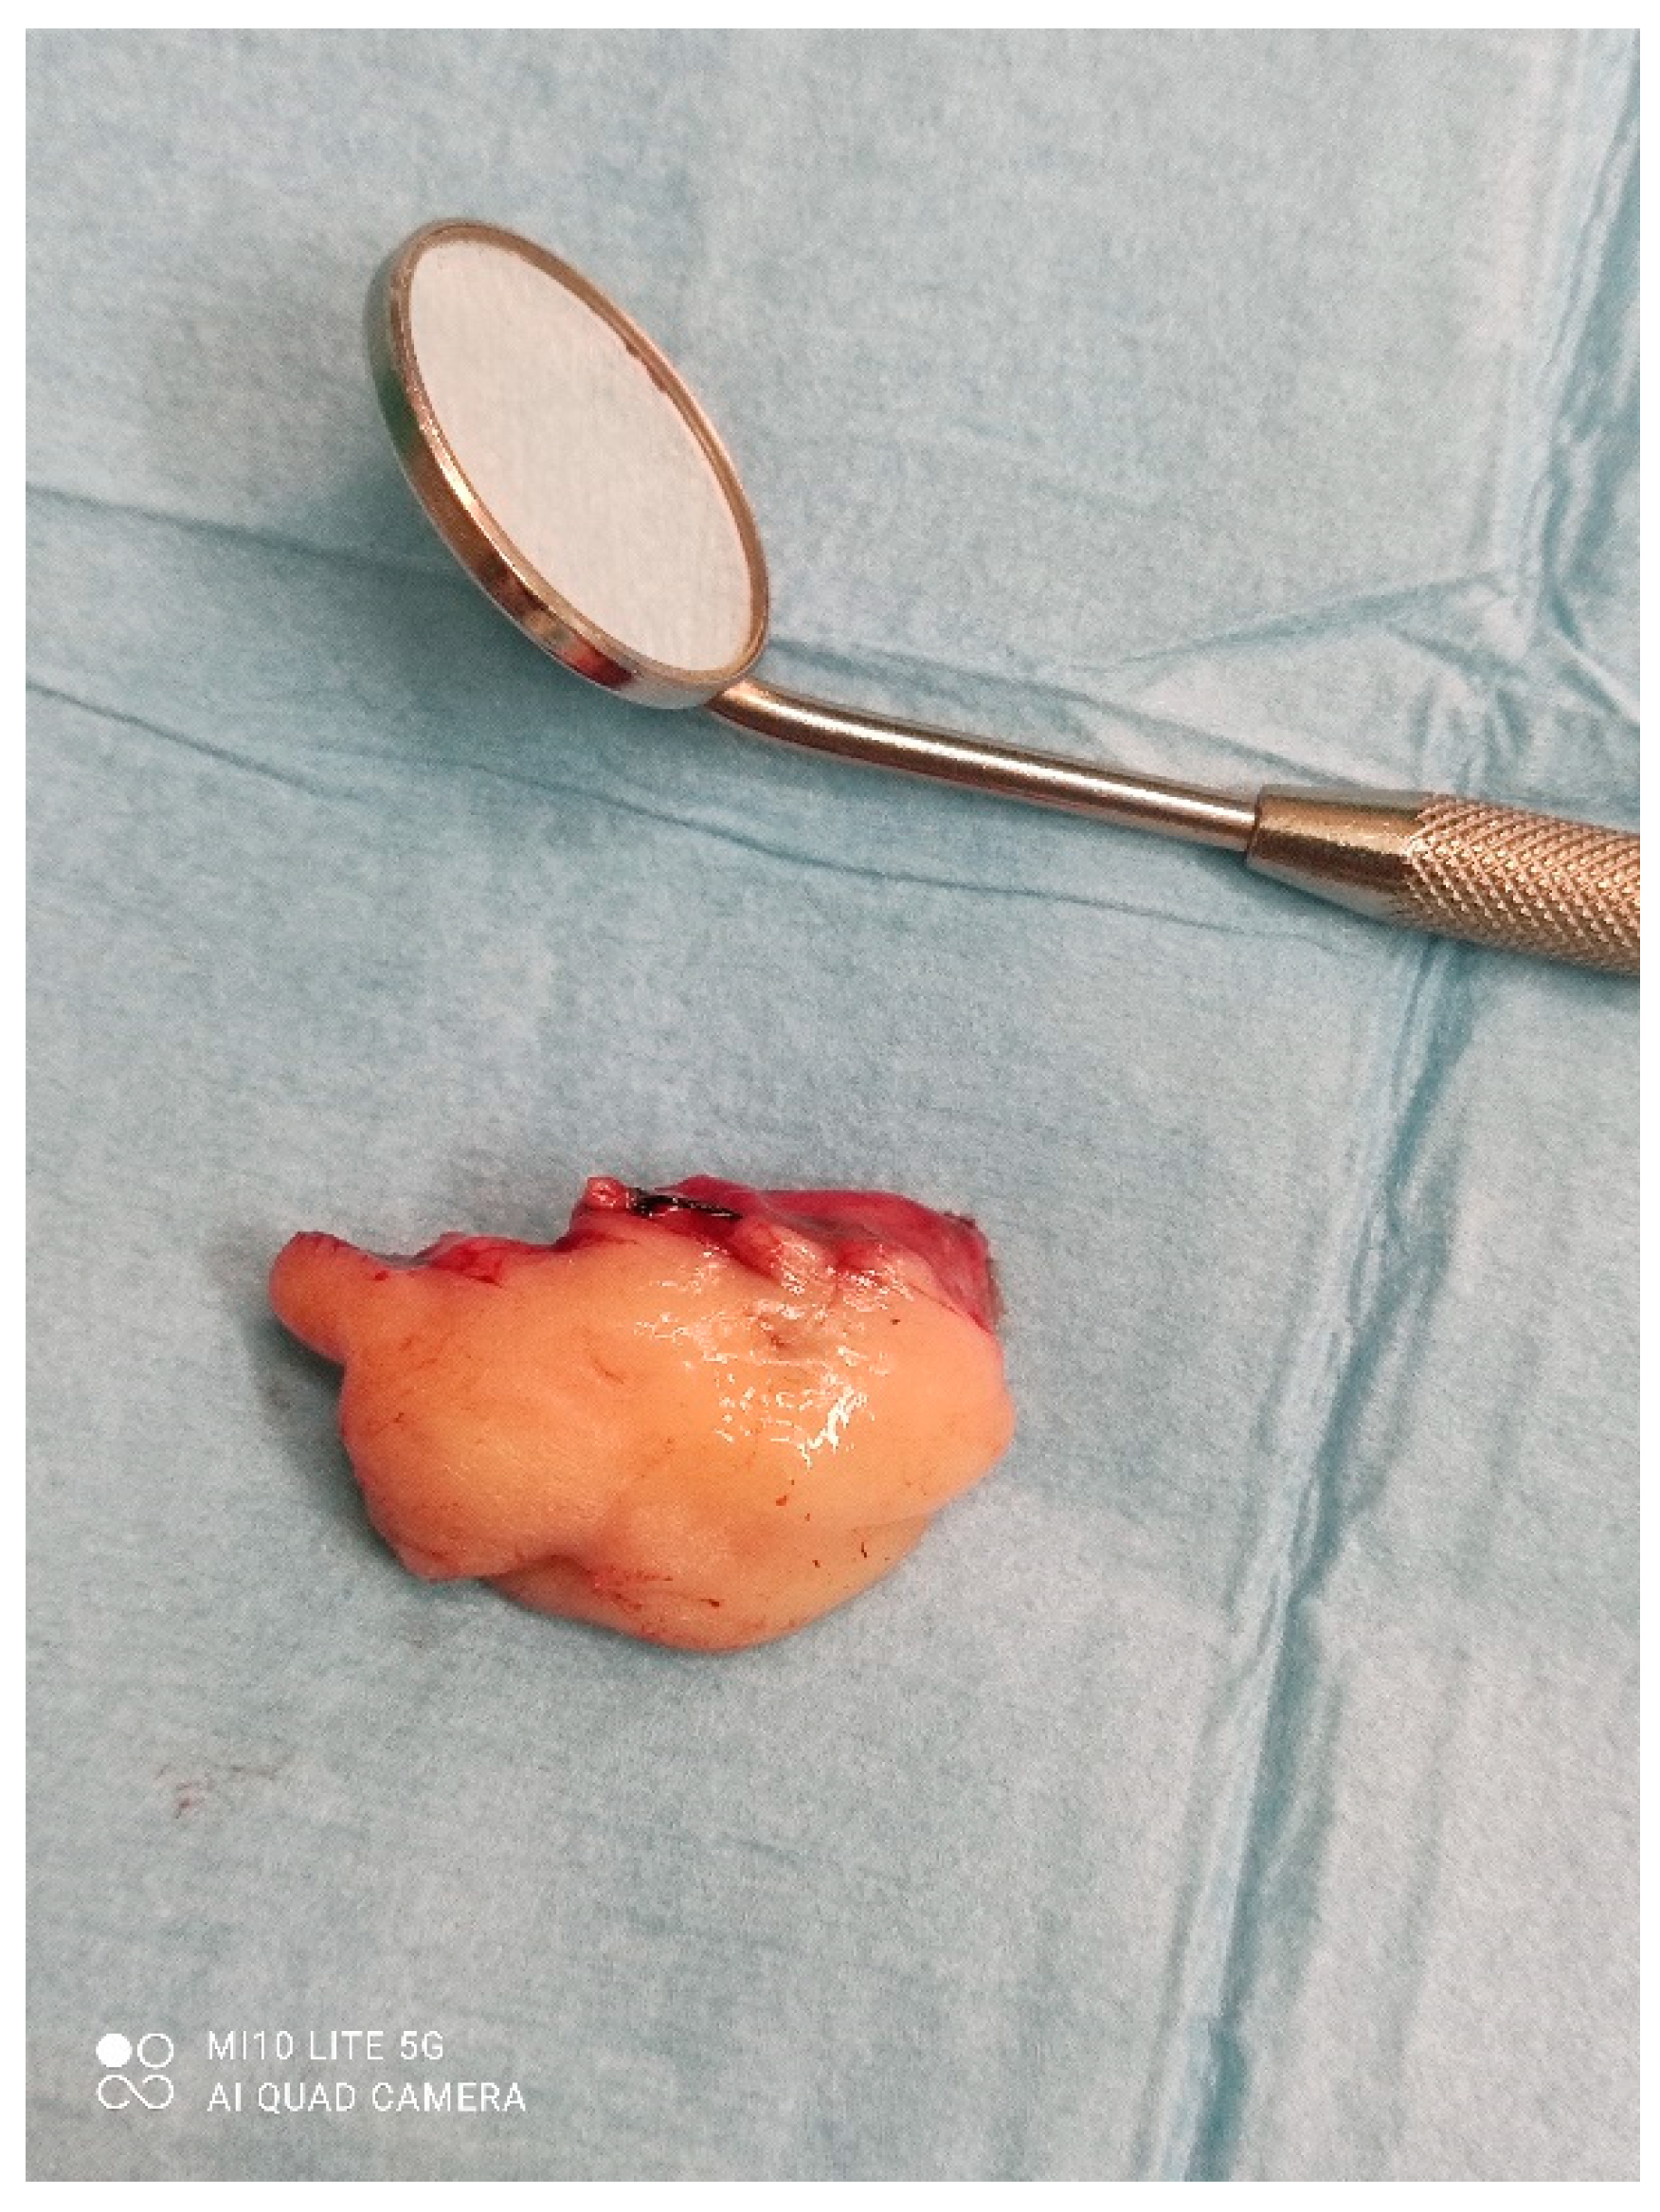

A male 70-year-old patient came to the Department of Oral Surgery, University Hospital Centre Zagreb with a voluminous fibrous mass in the distal region of the left mandible (Figure 1). The patient has two acrylic bridges on four implants. The implants were placed six months prior to admission to the clinic, before the patient noticed the appearance of the mass. The acrylic bridges are 3 months old. The patient states feeling “swelling in the back part of the left mandible three months before coming in for a checkup”. Panoramic radiograph and CBCT did not show any radiolucency, radiopaque areas or signs of periimplantitis around the implants in the bone (Figure 2). The lesion has a smooth surface, with no ulcerations. It was on a broad base connected, with the sublingual anatomical region. The patient has poor oral hygiene, smokes and consumes alcohol: about two to three glasses of wine or beer a day. The palpation of the mass indicated that it was fixed to the alveolar crest of the left mandible on a wide base and was spreading to the left sublingual area. The measured size of the mass was 3.5 × 2 cm. After conducting a clinical examination, the differential diagnosis was possible irritation fibromatosis, peripheral gigantocellular fibroma or peripheral ossifying or non-ossifying fibroma, as well as a malignant mass, and the final diagnosis will be reached after the final PHD analysis. The final decision was an excision in toto (Figure 3). The mass was approached and the layers of submucosa were divided with a scalpel and an electro knife. During operation, it was noticed that the mass has a belonging artery connected to the left sublingual area. The artery was ligated with a resorbing thread 4/0 and the mass underwent complete excision (Figure 4). Parts of the flap were left to heal per secundam, but most of the incision towards the sublingual region was stitched with a non-resorbing silk thread 4/0 (Figure 5 and Figure 6). A full hemostasis was achieved by electrocauterization of the bleeding areas. The excison was performed under local anesthesia. Clinical, medical examination and removal of sutures were performed seven days after surgery (Figure 7).

Figure 5. Size of the mass.